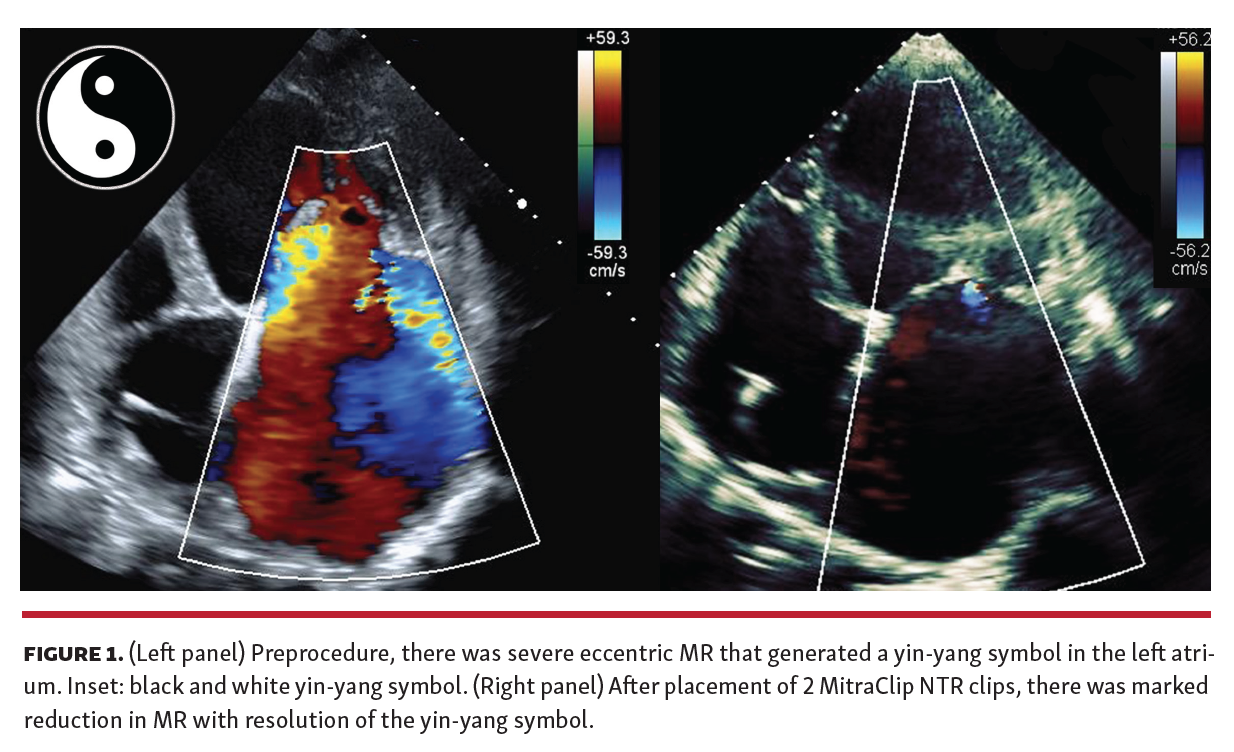

In select patients with severe, eccentric mitral regurgitation (MR), we have observed that the regurgitant jet may entrain blood along the left atrial wall to produce a Chinese yin-yang symbol on color Doppler. The Chinese yin-yang symbol consists of a circle divided by an S-shaped line into black (yin) and white (yang) segments, with yin (representing darkness) and yang (representing light) complementing each other harmoniously. Classically, this symbol has been described to represent the color Doppler appearance of circular blood flow related to high-flow arterial pseudoaneurysms.

An 81-year-old woman with symptomatic, severe, functional MR secondary to non-ischemic cardiomyopathy was referred for transcatheter mitral valve repair. Her transthoracic echocardiogram (TTE) demonstrated ejection fraction of 35%, left ventricular end-systolic dimension of 6.41 cm, severe left atrial and mitral annular dilation, and 4+ eccentric MR that generated systolic pulmonary vein flow reversal and a prominent yin-yang symbol (Figure 1). Quantitative evaluation demonstrated effective regurgitant orifice area of 46 mm2 and regurgitant volume of 72 mL. After placement of 2 MitraClip NTR clips (Abbott Vascular) to the A2-P2 segment, there was significant reduction in the patient’s MR evidenced by resolution of the yin-yang sign and normal systolic pulmonary vein flow.

We demonstrate a patient with severe, eccentric MR whose regurgitant jet generated a yin-yang symbol. We have observed this unique color Doppler finding in other patients with severe eccentric MR and it has not been previously reported.